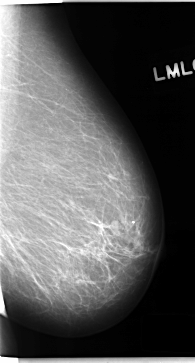

C_0155_1.LEFT_MLO

LEFT_MLO LINES 4712 PIXELS_PER_LINE 2528 BITS_PER_PIXEL 12 RESOLUTION 50 NON_OVERLAY